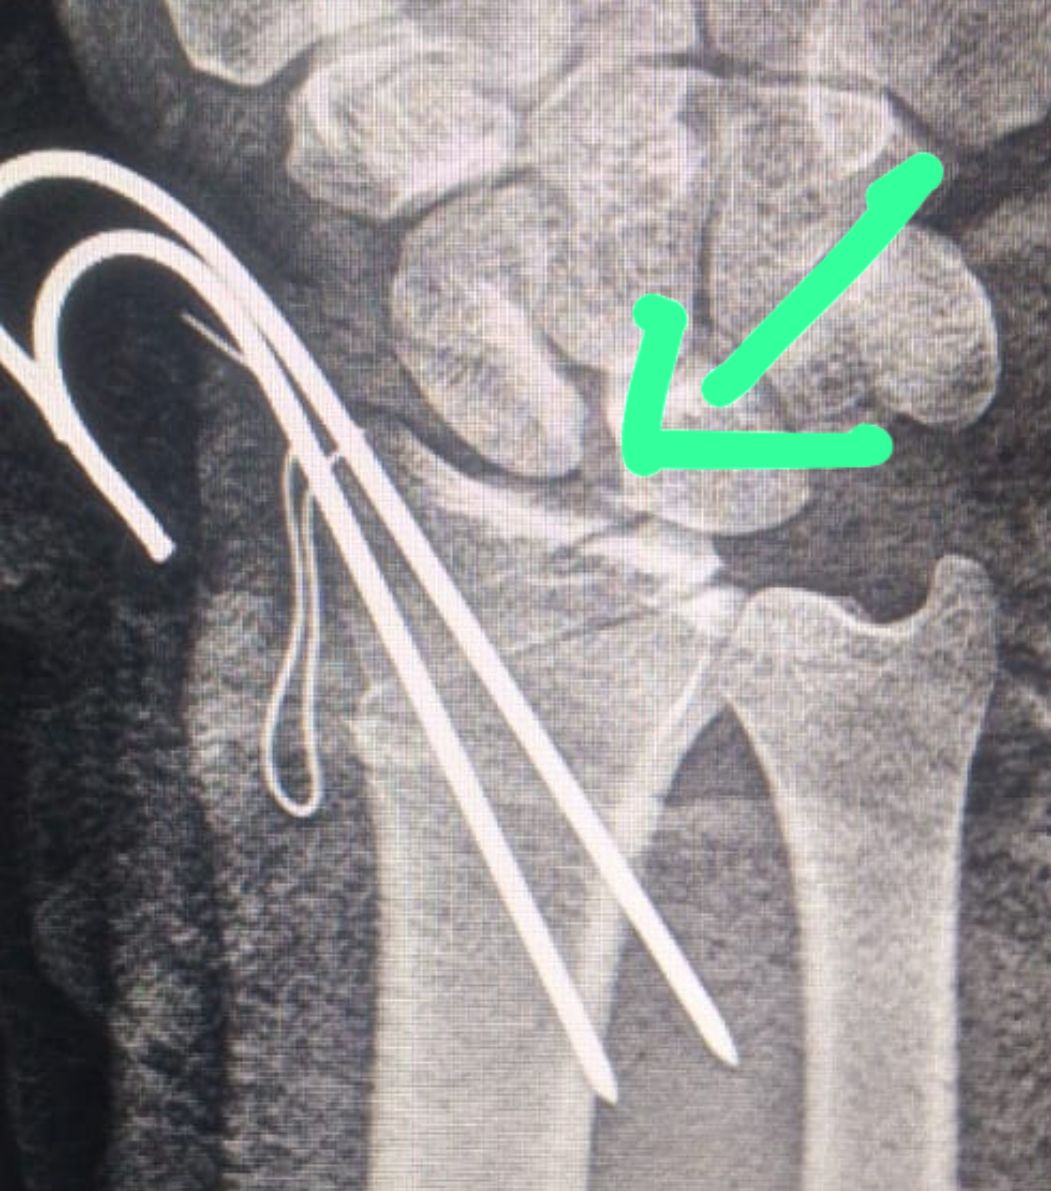

وأضاف مدكور أن حالة المريض كانت حرجة للغاية، إذ وصل إلى قسم الطوارئ وهو يعاني من بتر شبه كامل باليد اليمنى إثر إصابة قطعية عنيفة بآلة حادة، امتدت لتشمل الأوتار، والشرايين، والأعصاب الطرفية، إضافة إلى العظام والمفصل الرسغي، مع نزيف شديد وفقدان شبه تام للحركة والإحساس.

وأوضح الدكتور أحمد البيلي، وكيل المديرية للطب العلاجي، أن الفريق الطبي تعامل بسرعة واحترافية عالية مع الحالة، وتم نقل المريض فورًا إلى غرفة العمليات، حيث جرت الجراحة بدقة متناهية، باستخدام الميكروسكوب الجراحي لإعادة توصيل الأوتار القابضة والباسطة، وربط الشرايين لإعادة التروية الدموية، وإصلاح الأعصاب الطرفية باستخدام خيوط ميكروسكوبية فائقة الدقة.